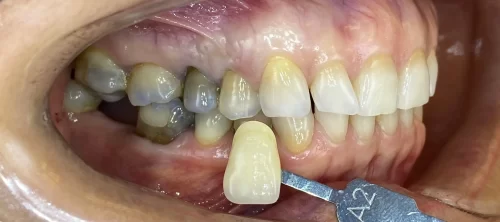

Tímea, kiterjedt amalgám tömések miatt elszíneződött fogait kerámia leplezésű cirkónium koronákkal láttuk el.

A metszőfogak közötti rést kompozit tömőanyaggal zártuk a páciens kérésére.